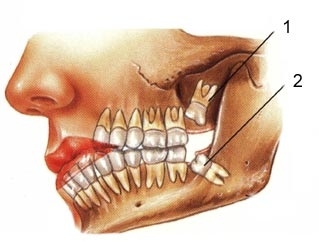

Xử trí răng mọc ngầm

TheoTS.BS.Nguyễn Phú Thắng : Răng ngầm là một hay nhiều răng nằm trong xương hàm trên hay xương...

Nhổ răng khôn mọc dại!!!

Răng khôn là răng hàm cuối cùng của mỗi bên hàm còn nói theo y khoa là Răng...